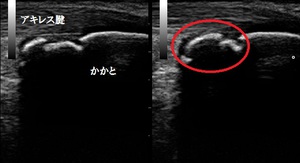

左踵(健側) 右踵 超音波長軸像 同部5週後

歩行時に踵を突いて歩くと激痛が起こります。超音波検査の結果、右踵の成長軟骨部に剥離した不正像が

認められました(上画像の丸の囲み)。

4週後、剥離した軟骨の状態を客観的に評価するために超音波検査の予定です。

5週後の超音波検査の結果、初診時に剥離していた軟骨が骨癒合してほとんど左右差が無くなりました。

痛みも消失し、運動制限なく部活動を行っております。